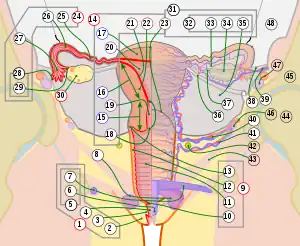

9. Vagina: 10. Hymen; 11. Lumen; 12. Wall; 13. Fornix (lateral)

14. Uterus: Parts: 15. Cervix; 16. Body and 17. Fundus. 18. Orifices: External and Internal; 19. Cervical canal; 20. Uterine cavity; Layers: 21. Endometrium; 22. Myometrium and 23. Perimetrium

24. Fallopian tube: 25. Isthmus; 26. Ampulla; 27. Infundibulum; 28. Fimbria (with 29. Fimbria ovarica)

30. Ovary

31. Visceral pelvic peritoneum: 32. Broad ligament (with 33. Mesosalpinx; 34. Mesovarium and 35. Mesometrium)

Ligaments: 36. Round; 37. Ovarian; 38. Suspensory of ovary

Blood vessels: 39. Ovarian artery and vein; 40. Uterine artery and veins; 41. Vaginal artery and veins

Other: 42. Ureter; 43. Pelvic floor (Levator ani); 44. Femoral head; 45. Hip bone; 46. Internal iliac vessels (anterior branches); 47. External iliac vessels; 48. Abdominal cavity